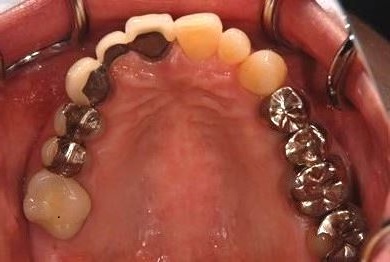

| 性別/年齢 | 女性 / 50歳 | ||||||||||||||||||||||||||||||||

| 主訴 | 銀のかぶせが取れたところと、痛みがある歯をセラミックで治療したい。 | ||||||||||||||||||||||||||||||||

| 治療内容 | メタルボンドセラミック3本(メタルボンドセラミッククラウン用土台3本) | ||||||||||||||||||||||||||||||||

| 総治療費 | 374,063円 | ||||||||||||||||||||||||||||||||

| 治療期間 | 10ヶ月 |